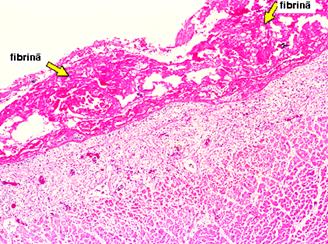

Pericardita acuta se defineste ca inflamatia ambelor foite pericardice produsa de o multitudine de cauze care pot sa nu aiba neaparat expresie clinica. Studii necroptice au relevat prezenta relativ frecventa de pericardita in absenta diagnosticului clinic. Histopatologia pericarditei acute depinde de cauza, dar trasaturile generale constau in hiperemie sau crestere a microvascularizatiei, infiltrate leucocitare (mai ales polimorfonucleare) si depuneri de fibrina cu aderente intre straturi sau intre pericard si structurile adiacente (pleura, mediastin).

ingrosare de pericard cu eventuale depozite de fibrina (uneori libere in lichid).

adenozin-deaminaza in lichidul pericardic (TBC). Ex. histologic de pericardita fibrinoasa →